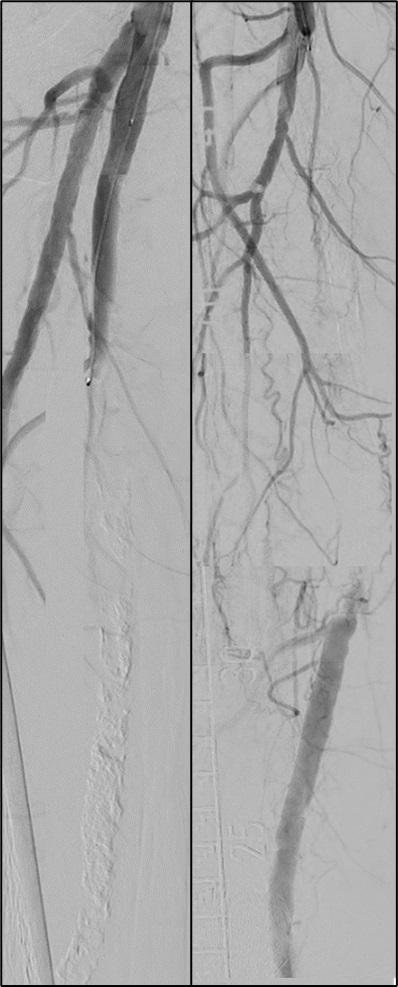

The inaugural Interdisciplinary Aortic Dissection Symposium (IADS; 6 September, London, UK) highlighted three trials— EARNEST, IMPROVE-AD and SUNDAY—all of which are set to provide some much-needed data on treatment options for uncomplicated type B aortic dissection (TBAD). Here, Tim Resch (University of Copenhagen, Copenhagen, Denmark) gives an update on SUNDAY, detailing enrolment progress and the challenges of conducting a randomised trial.

What is the SUNDAY trial?

The SUNDAY trial is a clinical study investigating the best treatment approach for patients with uncomplicated TBAD. It is a randomised, open-label trial conducted across the Nordic countries, including Denmark, Sweden, Norway, Finland, and Iceland.

The trial compares two treatment strategies for uncomplicated TBAD patients: standard medical therapy (SMT) alone versus SMT combined with thoracic endovascular aortic repair (TEVAR). SMT typically involves controlling blood pressure and providing pain relief, with β-blockers as first-line treatment.

What data are you hoping to gain from the trial?

The primary aim of the SUNDAY trial is to determine whether the addition of TEVAR improves fiveyear survival rates compared to SMT alone. Secondary outcomes include aortic-related mortality, neurological events, quality of life, reinterventions,

and healthcare costs. The trial aims to enrol around 554 patients and follow them for up to five years. The trial design is pragmatic, meaning it tries to reflect real-world practices by allowing flexibility in the type of TEVAR procedure performed and SMT management based on local protocols.

This study seeks to address a crucial question: does early intervention with TEVAR offer significant survival benefits in uncomplicated cases of TBAD? Previous research suggested potential benefits, but larger, randomised trials like SUNDAY are needed to provide definitive answers.

How is enrolment going?

The SUNDAY trial has initiated all 21 major vascular centers in the Nordics and enrolled 60 patients to date.